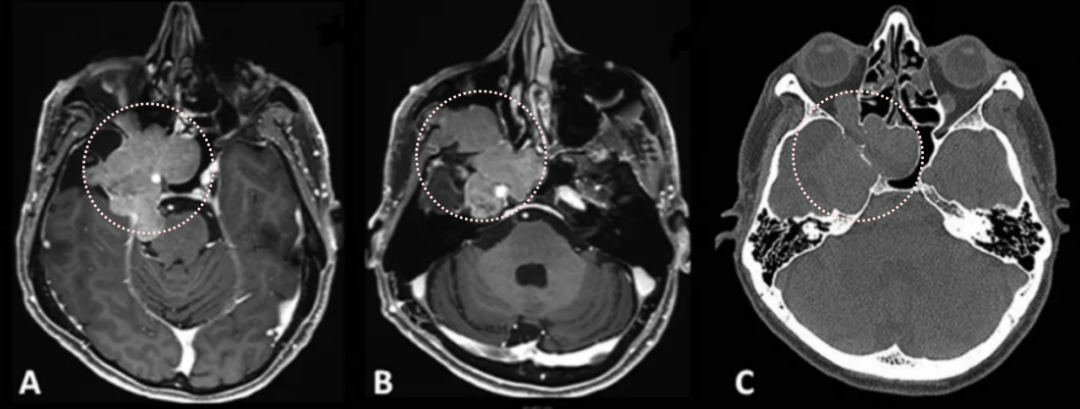

术前影像显示:

(A) 轴位T1加权钆增强MRI显示脑膜瘤延伸至后颅窝、海绵窦、眼眶和蝶窦

(B) 肿瘤延伸至中颅窝、翼腭窝和颞下窝

(C) 轴位CT显示蝶骨大翼侵蚀和蝶窦受累